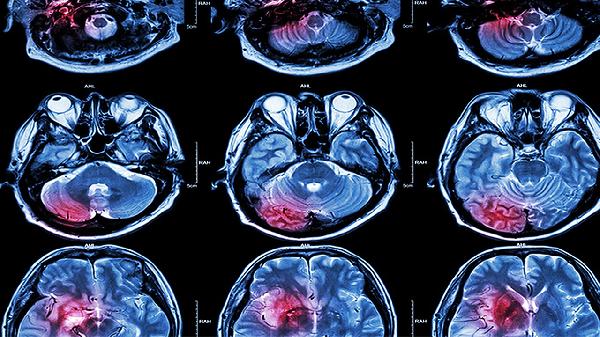

脑溢血前会有哪些早期信号

在脑溢血发生前,可能会出现一些明显的身体信号,比如头痛、眩晕、肢体麻木、说话困难、视力模糊等。脑溢血通常由高血压、脑血管异常或动脉瘤破裂等因素引发,一旦发现这些症状,应立即寻求医疗帮助。